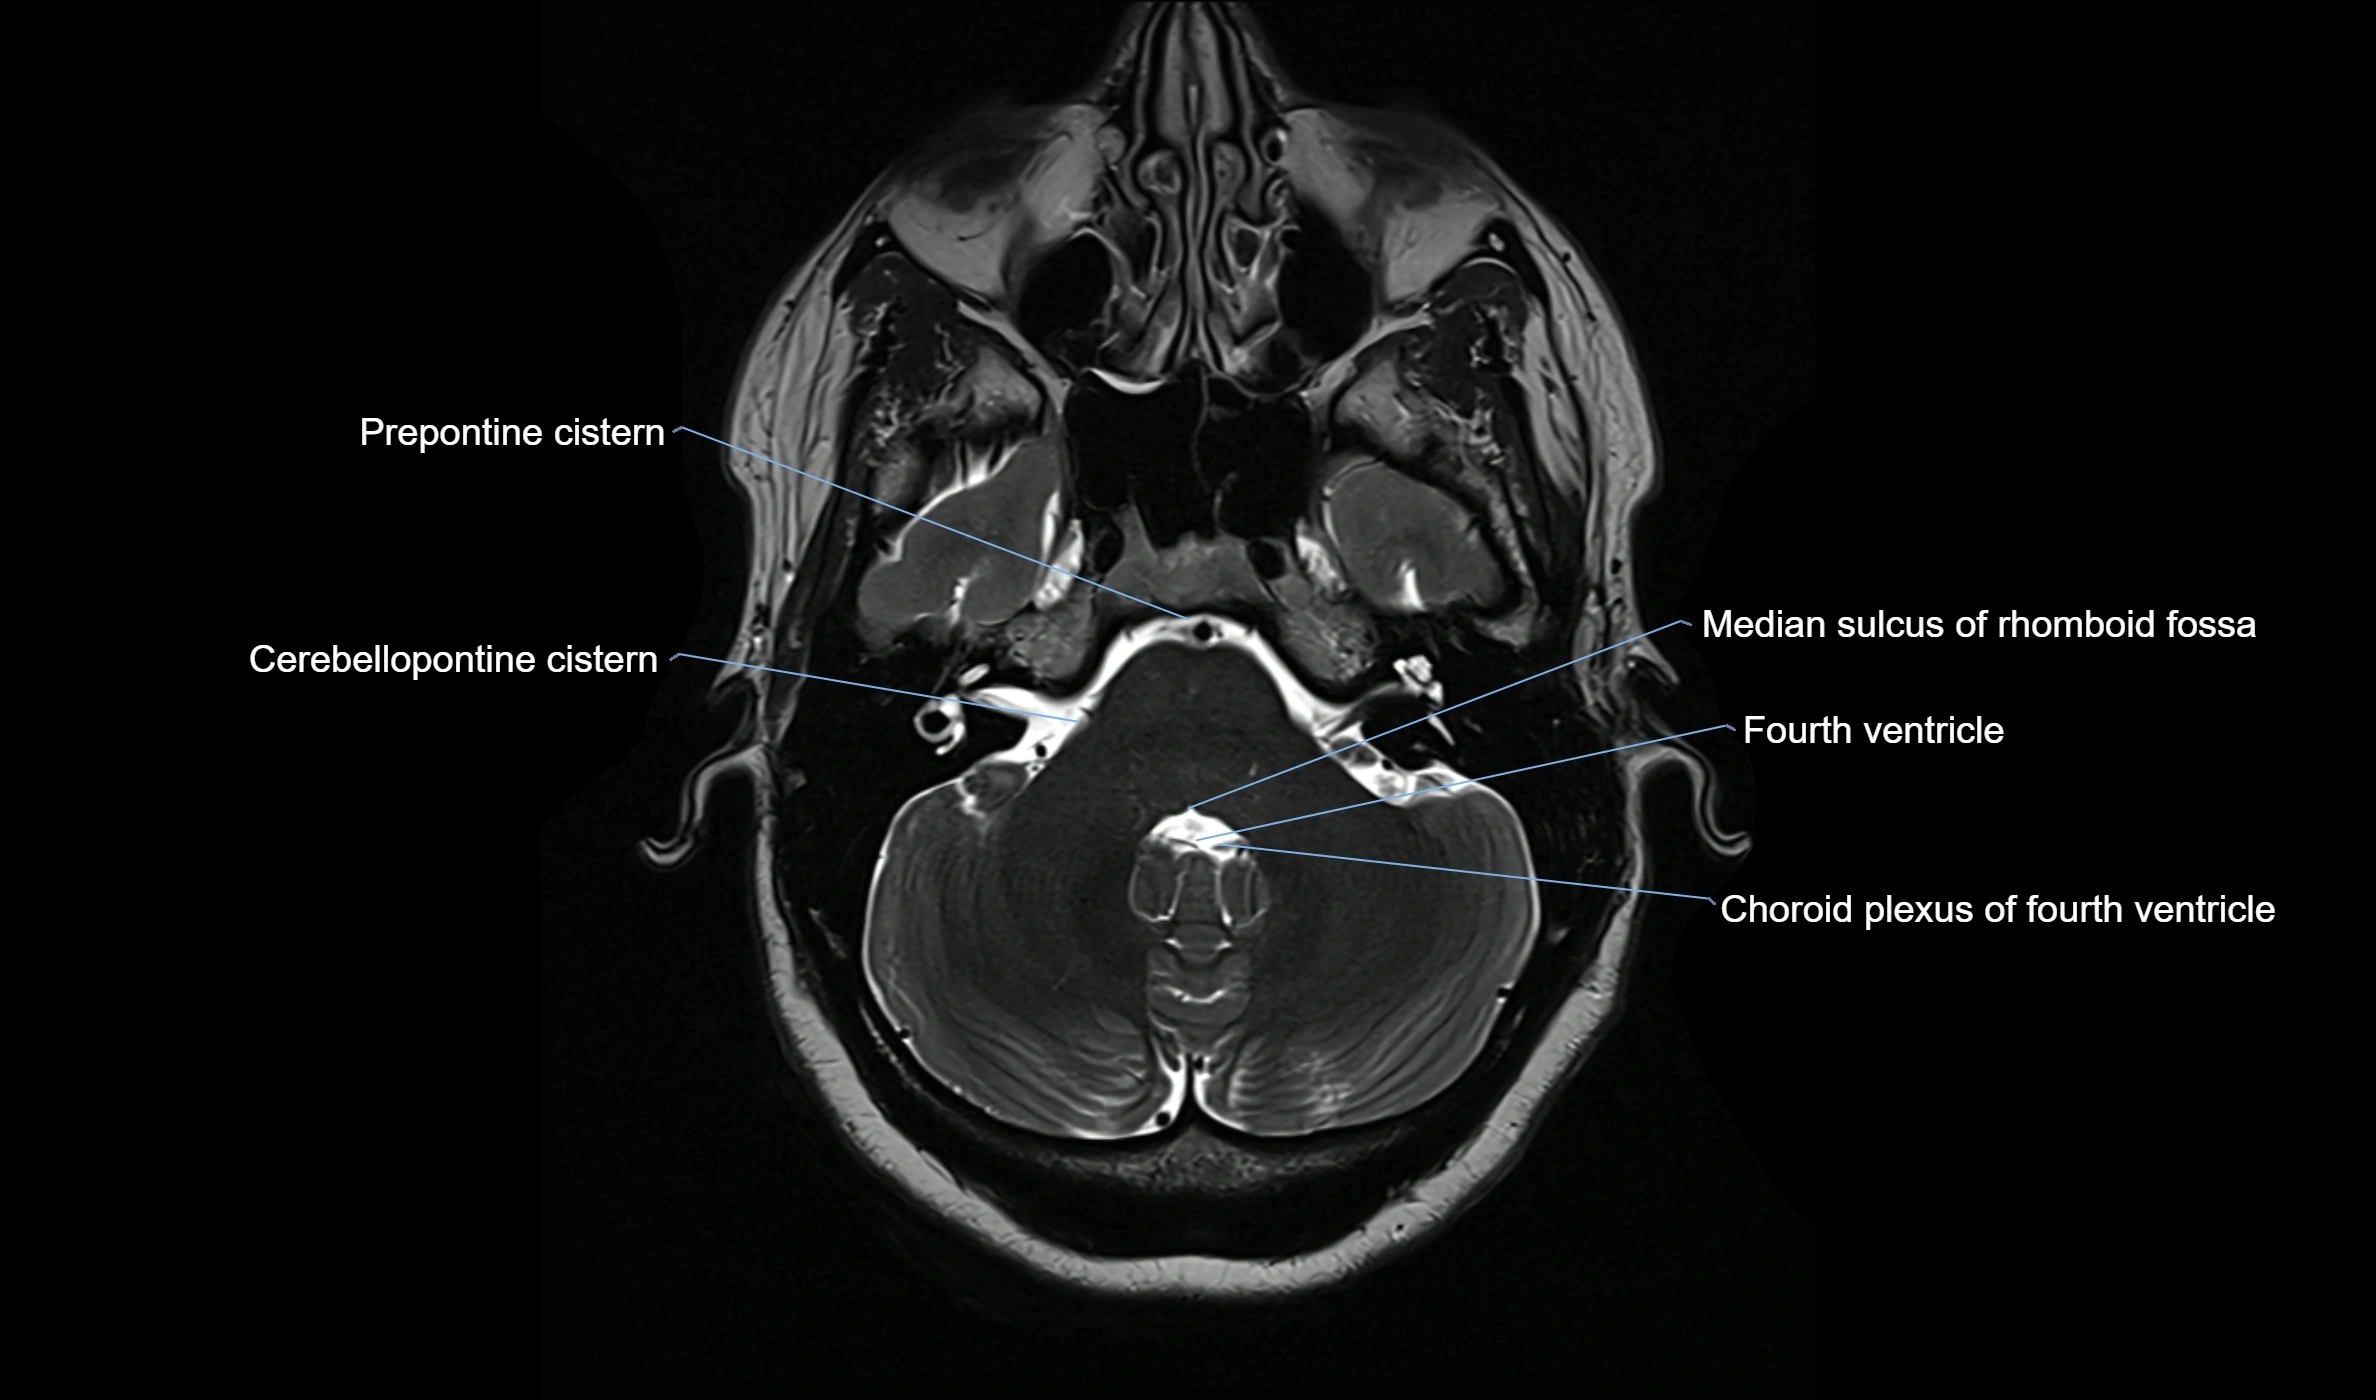

MRI images

image